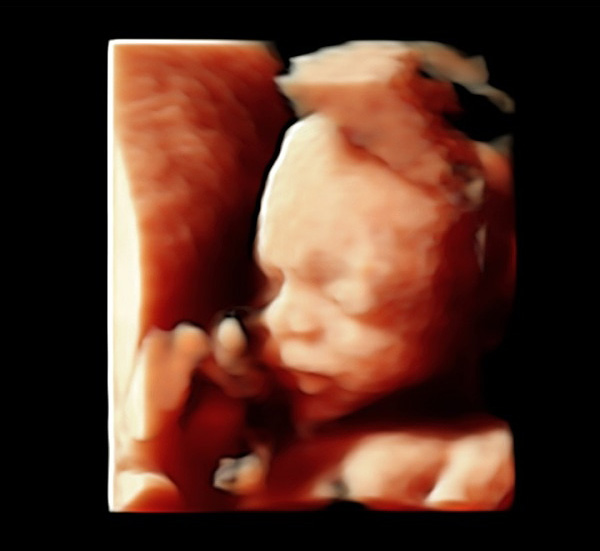

Detaylı ultrason, ikinci düzey ultrason ve ayrıntılı ultrason aynı anlama gelir. Renkli ultrason veya 4 boyutlu ultrason detaylı ultrasonla aynı şey değildir. 4 boyutlu ultrasonda bebeğinizin yüzü veya organlarının güzel bir anı olarak saklanacak fotoğrafı alınır. Detaylı ultrasonda ise bebeğin bütün organları ultrason teknolojisi el verdiğince incelenir

Detaylı ultrasonun yapıldığı cihazın görüntü kalitesi çok iyi olmalıdır. Ayrıca detaylı ultrason için kullanılan cihazın doppler özelliğinin olması gerekir. Yüz gibi bazı kısımlar iki boyutlu ultrasondan ziyade dört boyutlu ultrasonla daha iyi değerlendirilir.

- Bebeklerin genel yüz profilleri, burun kemikleri ve gözlerinde bulunan lenslerin izlemesi yapılır.